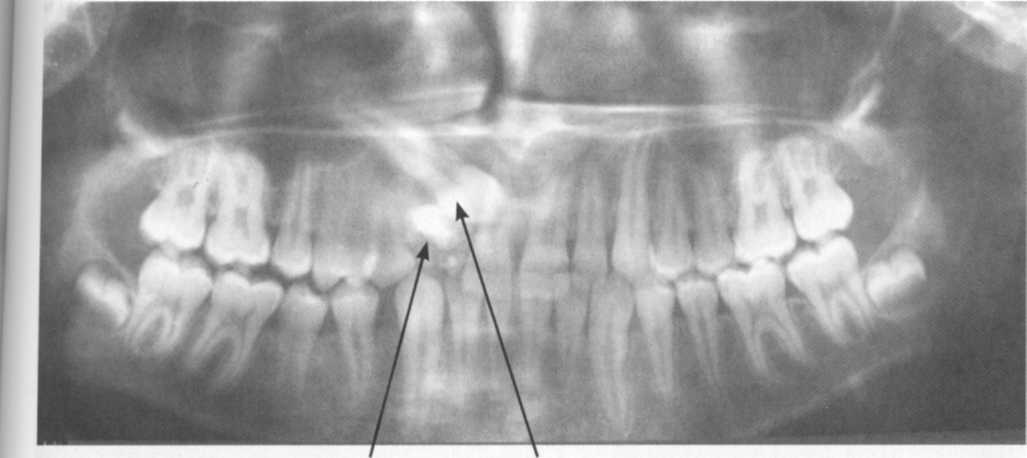

Одонтома нижней челюсти: фотографии и медицинская информация

Раздел: Фотобанк решений